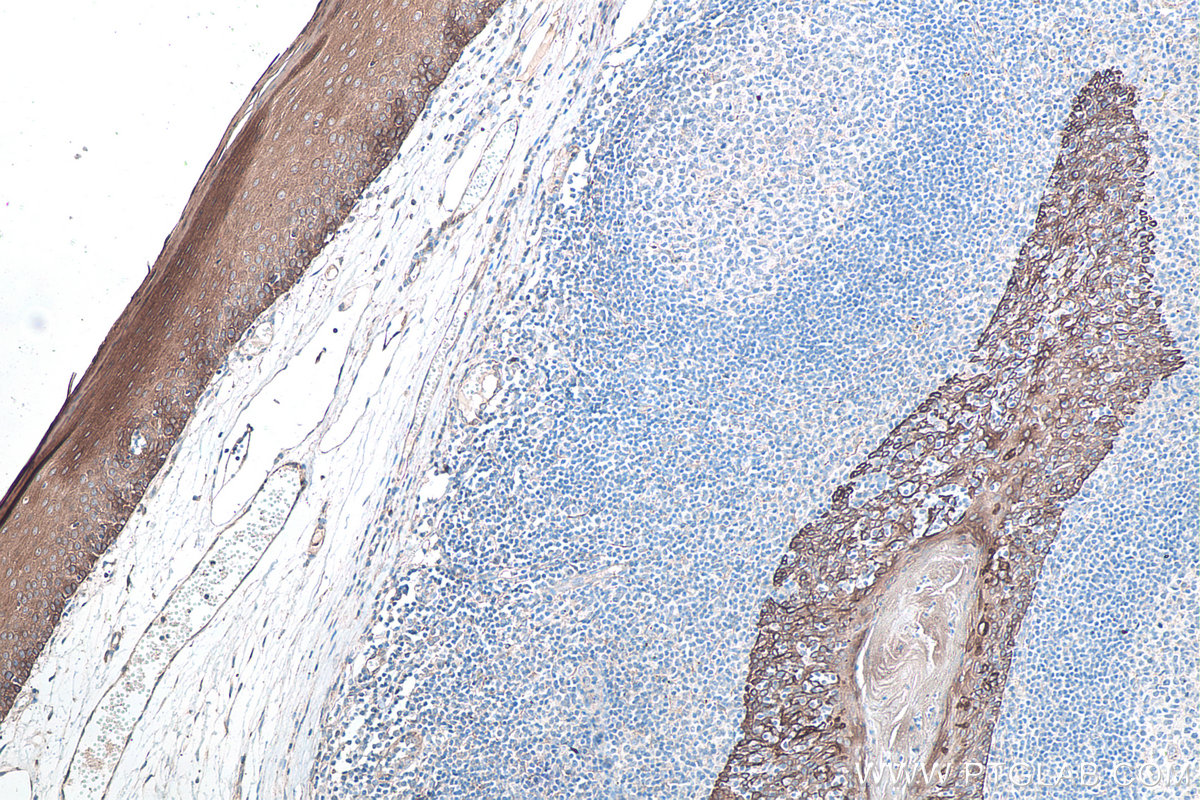

| Positive IHC detected in | human tonsillitis tissue, human appendicitis tissue, human bowen disease tissue, human breast cancer tissue, human colon tissue, human liver tissue, human renal cell carcinoma tissue Note: suggested antigen retrieval with TE buffer pH 9.0; (*) Alternatively, antigen retrieval may be performed with citrate buffer pH 6.0 |

| Immunohistochemistry (IHC) | IHC : 1:3000-1:12000 |

10384-1-AP targets Cytokeratin 8 in WB, IHC, IF/ICC, IF-P, FC (Intra), IP, ELISA applications and shows reactivity with human, mouse, rat samples.

Cytokeratin 8 (CK8) is a protein that belongs to the cytokeratin family, which is a group of structural proteins found in the intracytoplasmic cytoskeleton of epithelial cells. CK8 forms intermediate filaments within the cytoplasm of simple epithelial cells, typically as a dimer with cytokeratin 18 (CK18). These filaments provide a stabilizing framework that helps determine cell shape and enables cells to cope with mechanical stress. CK8/CK18 filaments also serve as a mesh of "paths" for signaling molecules, metabolites, and pathogens to travel within the cell in an organized manner. CK8 is expressed in various epithelial tissues and is particularly associated with glandular and simple epithelia. Its expression is also a significant marker in several types of cancer, including lung and esophageal cancer, where it can indicate tumor progression and poor prognosis.